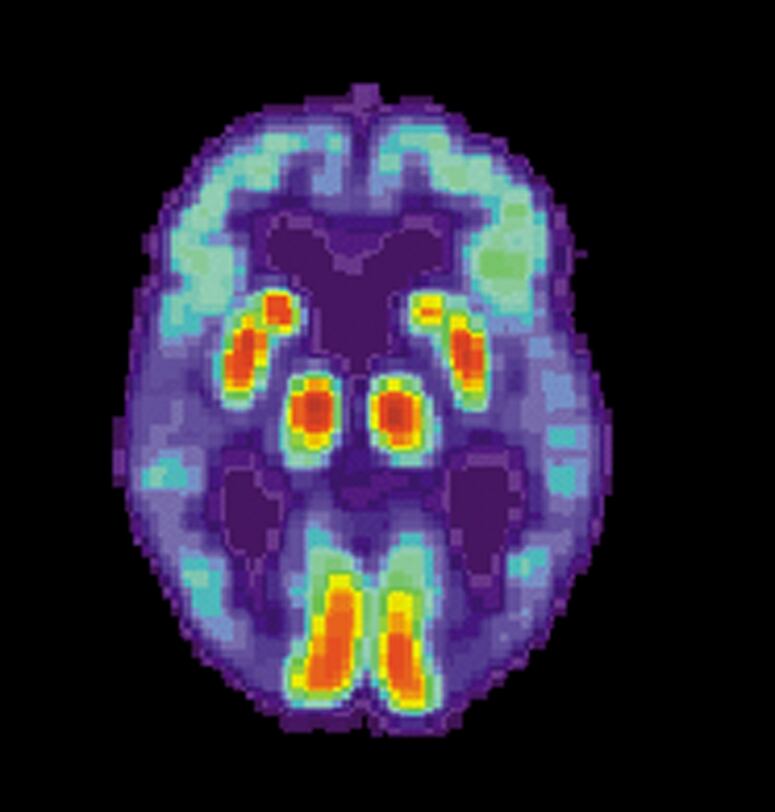

El alzhéimer es un mal neurodegenerativo crónico caracterizado por la pérdida progresiva de la memoria y de la capacidad de quienes lo padecen para realizar actividades básicas.